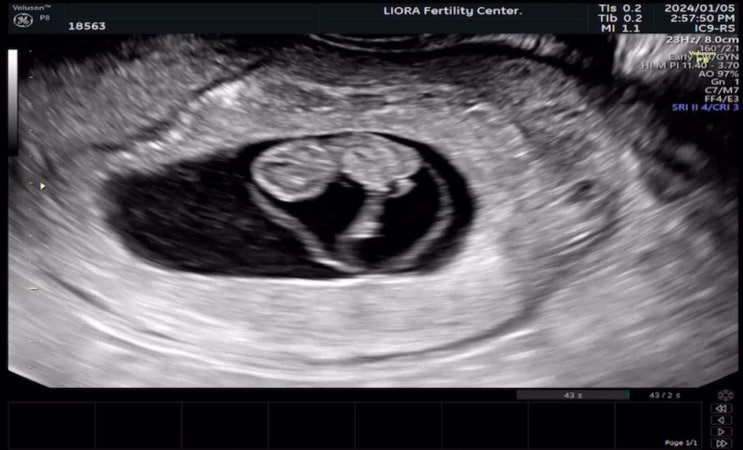

1-1 / 임신 9주차 증상 배 초음파 배랫나루 벌써...

리오라여성의원 졸업!! 비교적 짧았지만, 나에게는 길고 길었던 리오라여성의원 난임병원 졸업했다. 이 날...